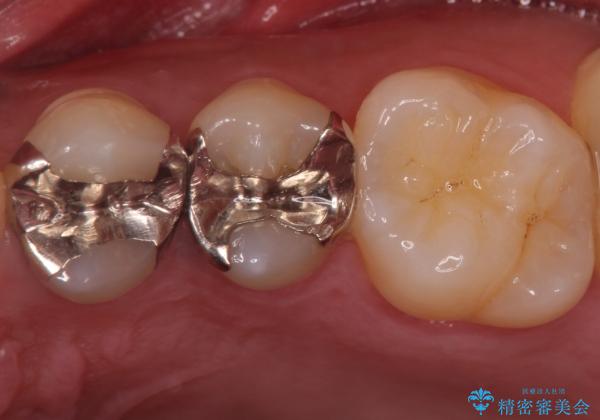

銀歯を目立たなくしたい セラミックインレーでの治療

セラミックインレーでの治療となります。

- 左上45 セラミックインレー 77,000円×2本 費用は治療当時の料金となります

奥歯とはいえ今回のようなケースでは笑った時に銀歯がちらつきます。

白く目立たないセラミックインレーが入ったことで大変喜んでいただけました。